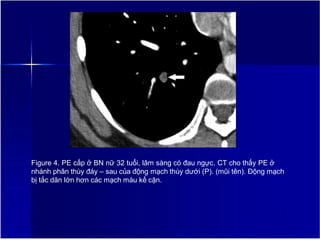

Figure 4. PE cấp ở BN nữ 32 tuổi, lâm sàng có đau ngực. CT cho thấy PE ở

nhánh phân thùy đáy – sau của động mạch thùy dưới (P). (mũi tên). Động mạch

bị tắc dãn lớn hơn các mạch máu kế cận.